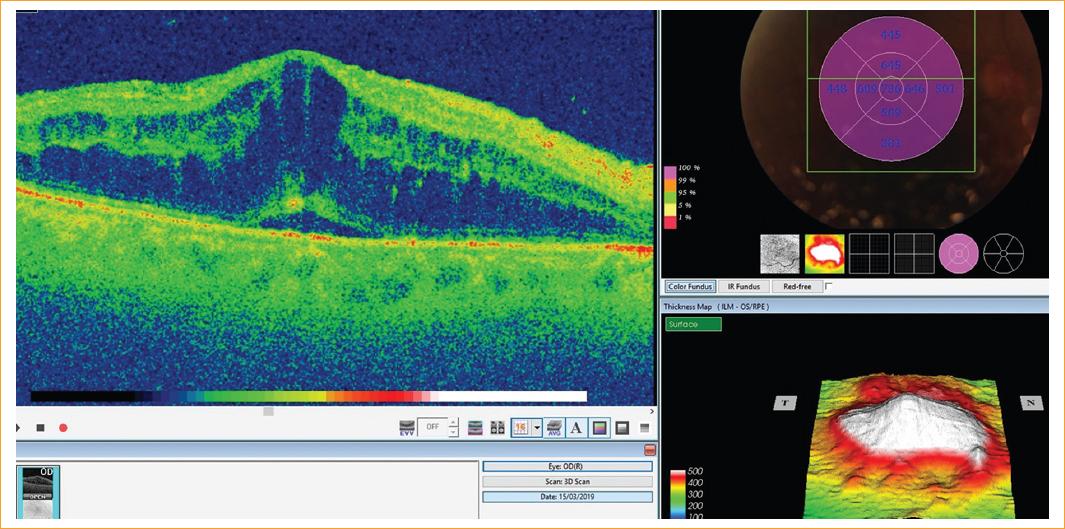

Diez meses después, el paciente volvió a ser derivado a la unidad de oftalmología tras sufrir una nueva pérdida de visión en el ojo derecho acompañada de un intenso dolor periorbitario que no había desaparecido con un tratamiento de pregabalina. Su agudeza visual se había establecido contando dedos a 1 metro de distancia y la fundoscopia realizada había revelado la presencia de papiledema en el disco óptico, hemorragias retinianas y exudados algodón-lana. La tomografía de coherencia óptica (OCT) confirmó la presencia de edema macular cistoide, razón por la cual se prescribió un nuevo tratamiento antiangiogénico. Dos semanas después, acude a urgencias con un cuadro de ptosis completa en el párpado derecho. Los movimientos extraoculares habían quedado abolidos por completo lo cual empeoró la agudeza visual del paciente (Fig. 1). El paciente también presentaba defecto pupilar aferente relativo. Las hemorragias retinianas y el edema macular se mostraron persistentes y la OCT reveló la presencia de engrosamiento de las capas retinianas por oclusión arterial acompañada de trombosis venosa (Fig. 2).

Figura 2 Apariencia de edema macular cistoide (EMC) en la tomografía de coherencia óptica con fluido subretiniano asociado.